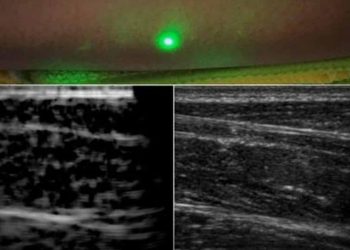

New laser system produces ultrasound images remotely

New York: Engineers at Massachusetts Institute of Technology have come up with an alternative to conventional ultrasound that does not ...